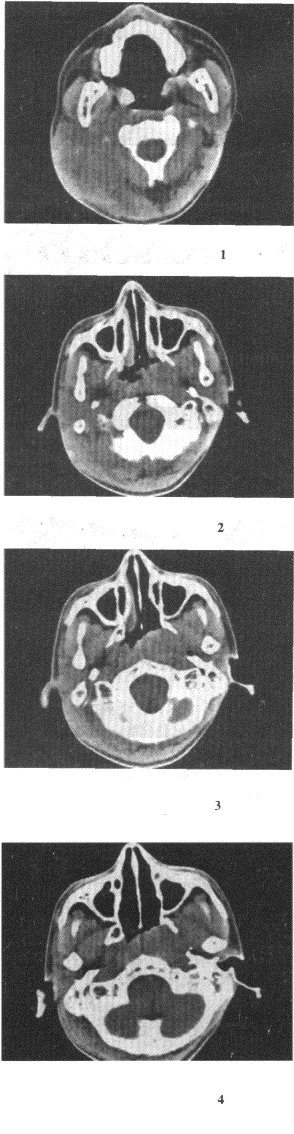

男,17岁,自诉鼻涕中带血3个月,伴耳鸣、听力减退,无发热,影像检查如图,最可能的诊断是()